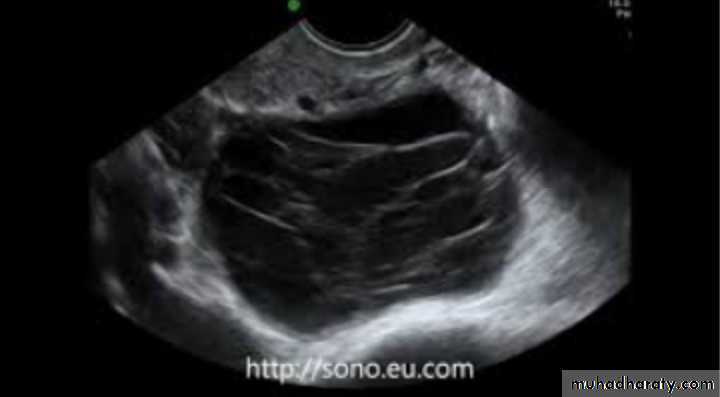

Large simple ovarian cyst

Tx only surgical removal

Dx: multilocular ovarian cyst

Risk: malignancy